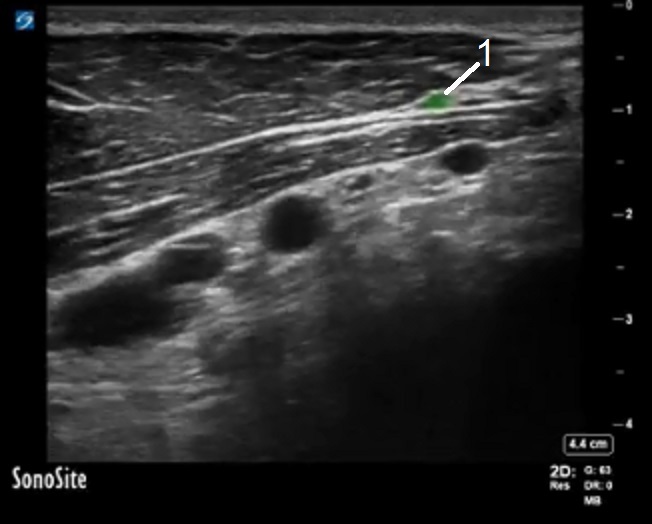

PECS Thoracoacromial Artery Image

Thoracoacromial Artery